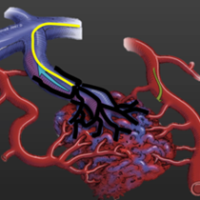

Retinoblastoma

Como o retinoblastoma é tratado? Existem várias maneiras de tratar o retinoblastoma....